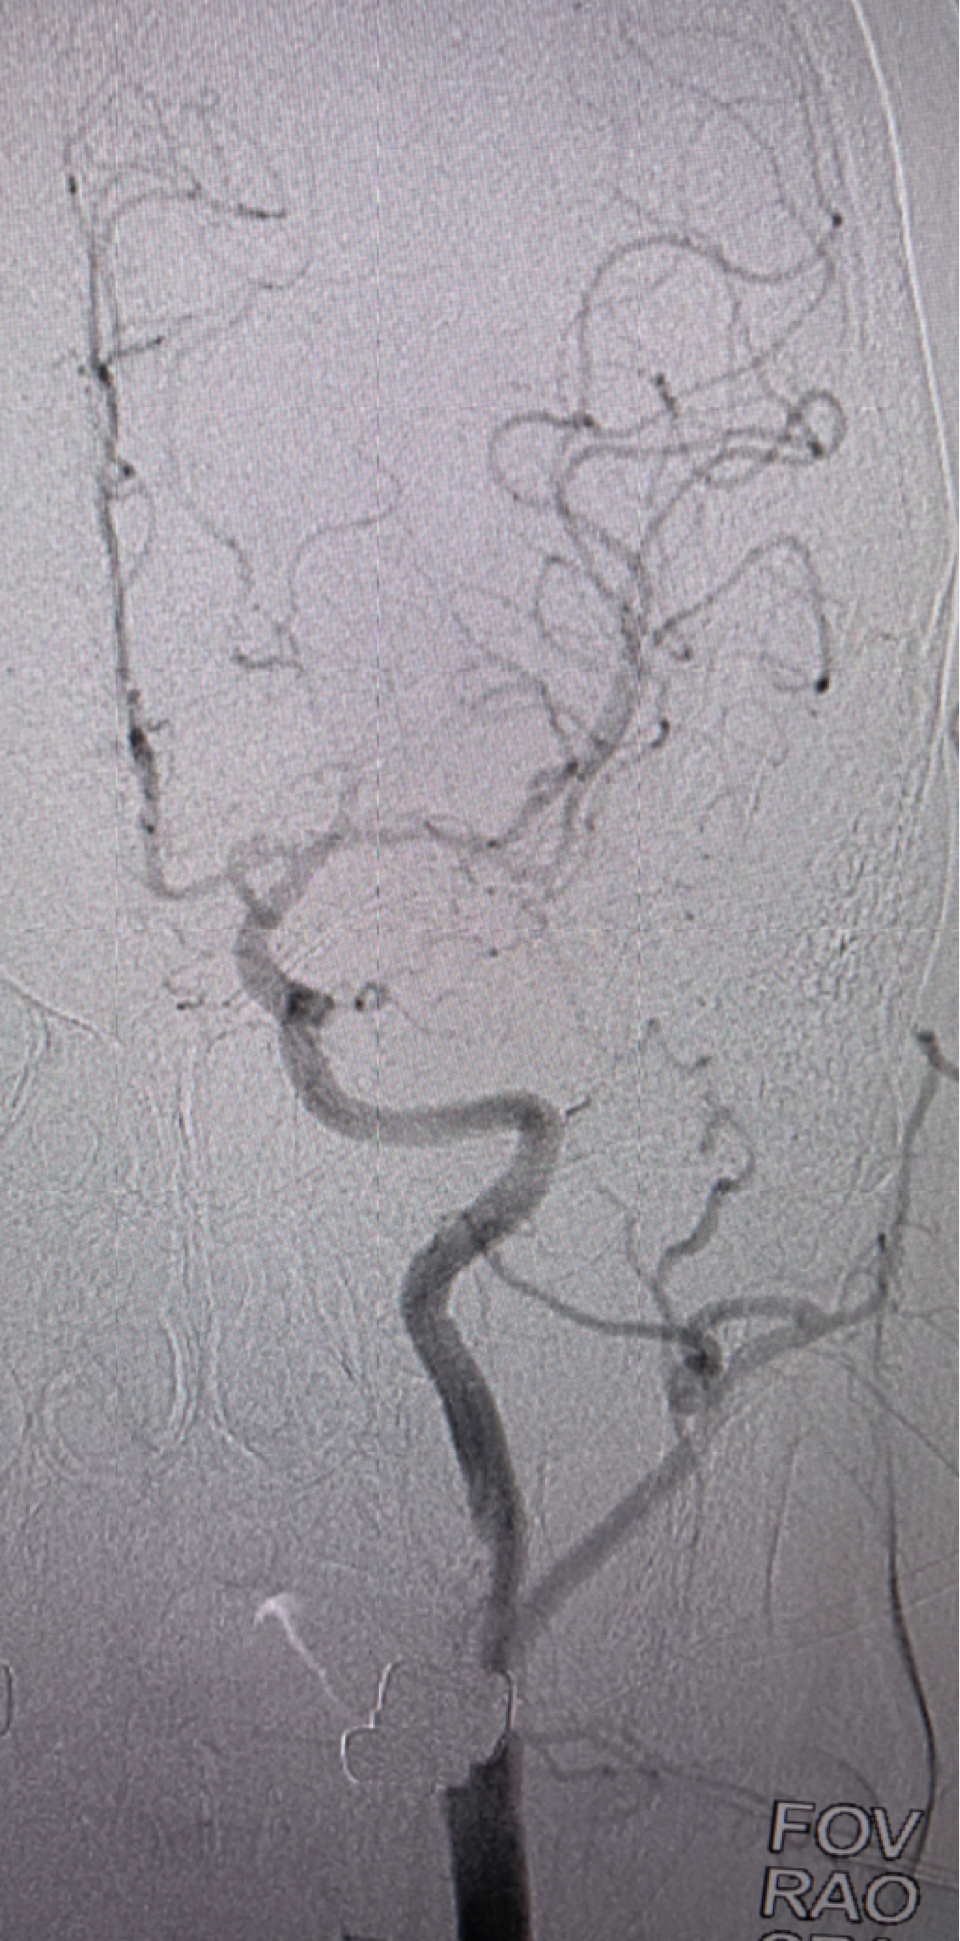

左侧颈内动脉正位造影提示前交通未开放